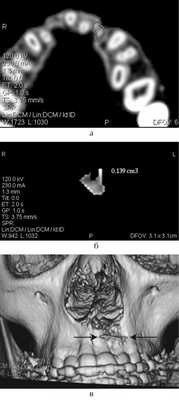

Ортодонтическое лечение после костной пластики проводилось под контролем за состоянием аутотрансплантата с помощью дополнительных методов диагностики — ЭОМ, УЗИ, спиральной компьютерной томографии (СКТ), что позволило оценить степень остеоинтеграции, либо резорбции костного регенерата (рис. 3).

Рис. 3. СКТ: 3D-реконструкция (а), аксиальный срез через 4 года после костной аутопластики (б), выделенный объем костного регенерата (в).